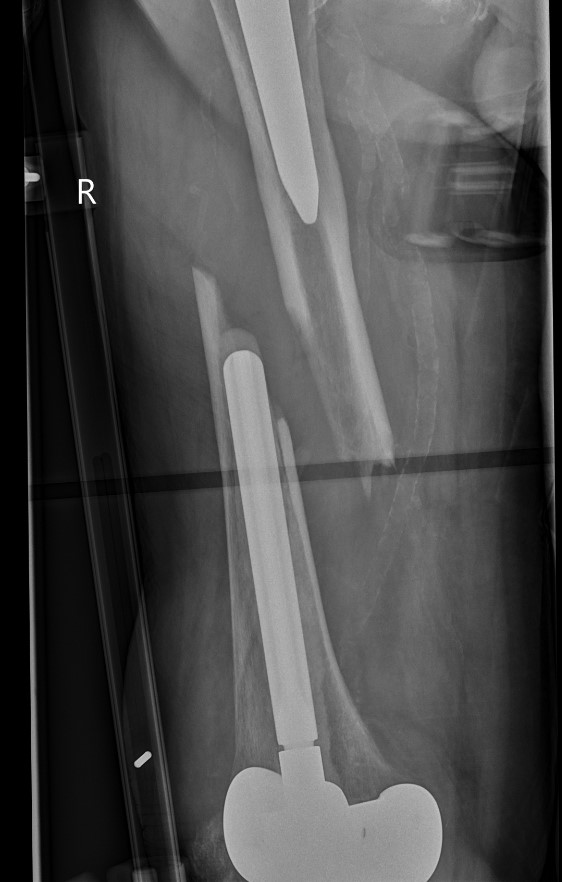

Long stem cemented revision

Long stem uncemented revision